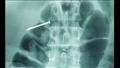

في ولاية راجستان غربي الهند، صُدم الجراحون عندما عثروا على 116 مسمارا حديديا بأحجام مختلفة، وسلك طويل، وحبيبة حديدية في جدار معدة شخص، بعد أن اشتكى من ألم شديد في المعدة، لحسن الحظ، نجا "بهولا شانكار" البالغ من العمر 42 عاما من الجراحة المحفوفة بالمخاطر التي استمرت ساعة ونصف، وفقا لصحيفة "هندوستان تايمز".

وقال الدكتور أنيل سايني، الذي أجرى عملية جراحية لـ"بهولا" في مستشفى حكومي: "إنه غير قادر على سرد كيف حدث له ابتلاع مثل هذه الكمية الضخمة من الأشياء، كان من الممكن أن تكون المسامير الحديدية قاتلة إذا دخل أي منها إلى أمعائه".